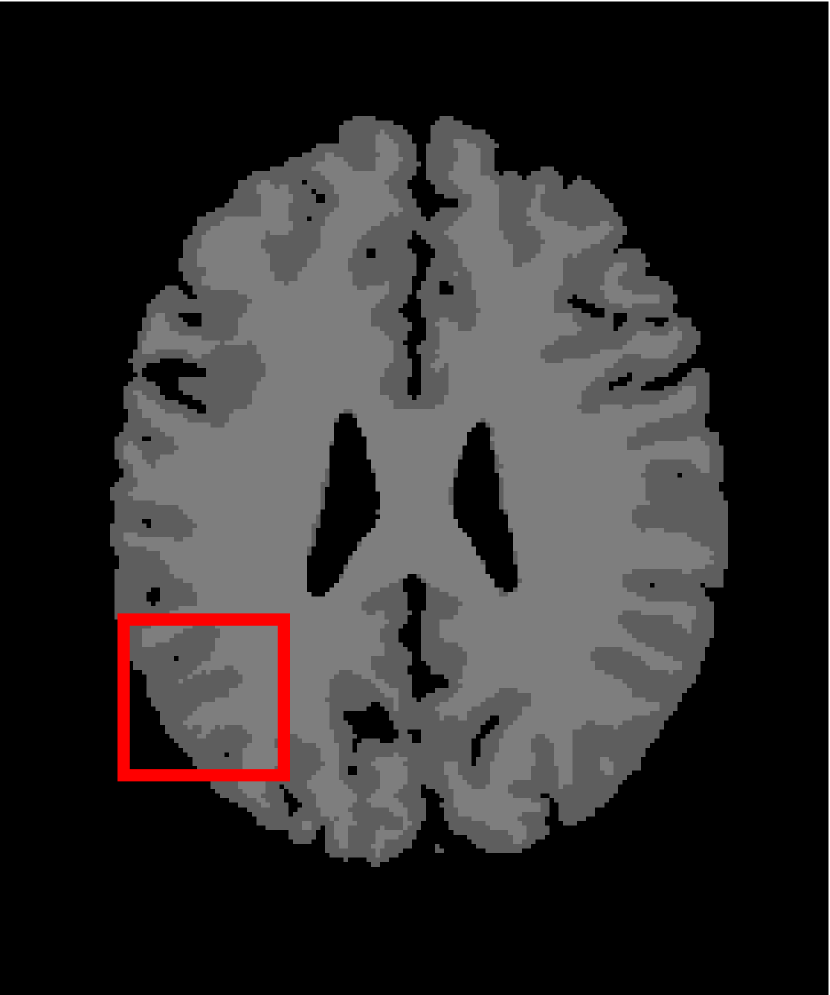

In the second experiments, we segment two medical images coming from a simulated brain database (BrianWeb): http://www.bic.mni.mcgill.ca/brainweb/. The two images are generated by T1 modality with slice thickness of 1mm resolution, 9% noise and 20% intensity non-uniformity. Here, the two images are represented two slices in the axial plane with the sequence of 100 and 110. Moreover, there are golden standard segmentations in the dataset. We set the numbers of clusters to 4. The visual comparisons are illustrated in Figs. 6 and 7.

Figure 7: Segmentation results for the second medical image. From (a) to (l): ground truth, noisy image and results of FCM_S1, FCM_S2, FGFCM, FLICM, KWFLICM, ARKFCM, FRFCM, WFCM, DSFCM_N, and LRFCM.

By focusing on the marked red square in Figs. 6 and 7, we easily find that FCM_S1, FCM_S2, FGFCM and ARKFCM are sensitive to noise. FLICM and KWFLICM are vulnerable to severe intensity inhomogeneity. FRFCM brings overly smooth results due to the use of gray level histograms. WFCM and DSFCM_N cause several contours to change. However, LRFCM acquires clear contours and suppresses noise adequately. Moreover, we find that the segmentation result of LRFCM is closer to ground truth.